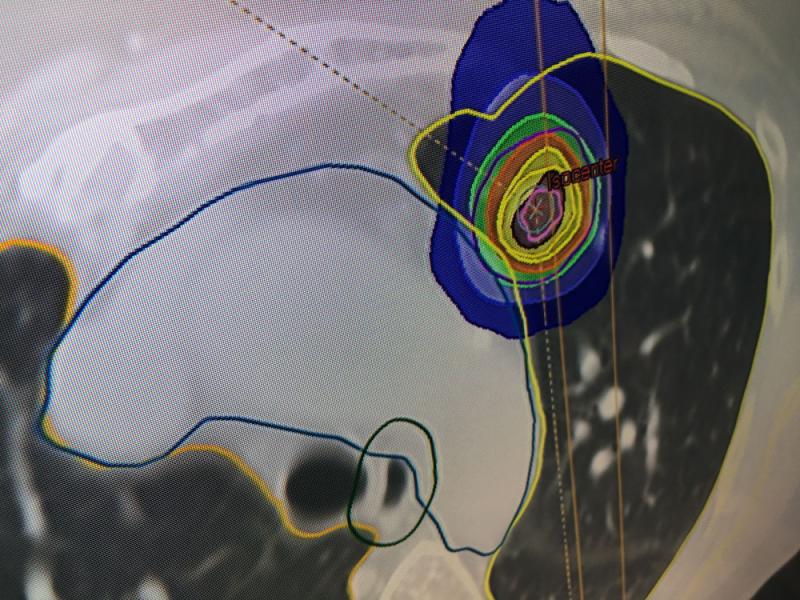

Below are photos from the American Society for Radiation Oncology (ASTRO) 2019 meeting September 2019 in Chicago. The annual conference has about 12,000 attendees. It is a showcase of the latest advances in radiation oncology technologies. Below are images of some of these radiation therapy technologies from the ASTRO expo floor with captions explaining them.